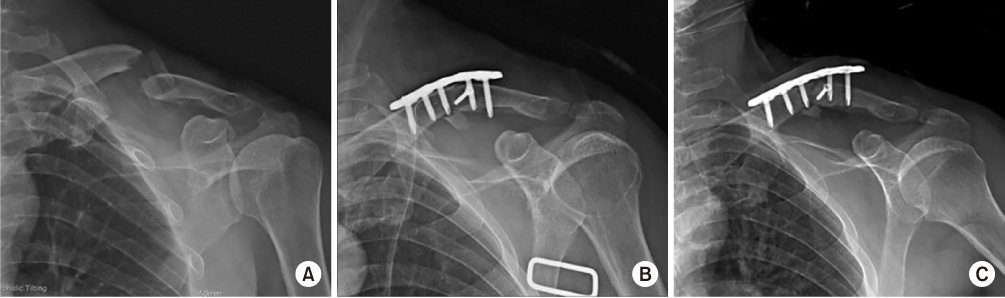

A 56-year-old, right-hand-dominant, male patient was transferred to our hospital for nonunion of mid-shaft clavicular fracture. The patient's first operation was performed at another hospital 5 months prior, where a plate and screws were implanted for repair (Fig. 1). His radiographs upon admission revealed loosening of the implant. On physical examination, he presented with left shoulder discomfort, tenderness along his fracture site of the left clavicle, and limited range of motion of the left shoulder secondary to pain. Neurovascular status was intact. When compared to radiographs obtained after the first operation, radiographs of the clavicle taken at admission demonstrated increased angulation of the fracture site with a visible fracture site gap and distal implant loosening (Fig. 1). He also had avascular necrosis of bilateral femoral heads. We performed a revisionary open reduction and internal fixation of the left clavicle with an autogenous cancellous bone graft from left femoral head after simultaneous left total hip arthroplasty. We recommended right total hip arthroplasty.

The surgery of the clavicle was performed by a shoulder specialist at our hospital. An incision was made along the clavicular axis on the previous operation scar. The previous plate and screws leaving out a lag screw were removed. Fibrous and granulated tissue of the nonunion site was excised and the ends of each fragment were prepared with curettage. Fracture reduction and fixation were achieved with a longer locking compression plate. The autogenous cancellous bone graft from the left femoral head was packed in the fracture gap after total hip arthroplasty. The wound was closed in a layered fashion after confirmation of satisfactory fracture reduction and implant position with an image intensifier (Fig. 2).

(A) Immediate postoperative radiograph after the second surgery. Callus bridging is seen on the 3-month follow-up radiograph (B) and consolidation processing on the 6-month follow-up radiograph (C).

On postoperative day 1, the patient presented with improved strength of thumb flexion and finger flexion to a grade 3/5 with decreased numbness of the left hand. On postoperative day 3, wrist extension improved to a grade 2/5 and left hand numbness was nearly resolved. Electromyography at 12 days postoperatively demonstrated diffuse brachial plexopathy, especially affecting the upper trunk. The patient underwent physical and exercise therapy until discharge. At the time of discharge, on postoperative day 30, thumb extension and finger extension and abduction were graded as 3/5, and all other left hand strengths were graded as 4/5. A Velpeau sling was not applied after discharge. On radiographs 3 and 6 months postoperatively, callus bridging and consolidation were visible (Fig. 4). On examination, there was no excess motion or tenderness at the fracture site, shoulder abduction and flexion were graded as 3/5 and 4/5, respectively, and all hand and elbow functions were fully recovered.